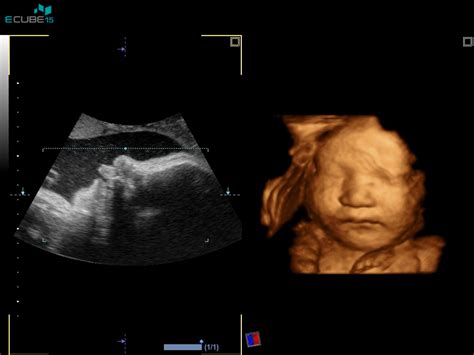

Ultrazvočno merjenje nuhalne svetline pri plodu je sodobna neinvazivna preiskava, ki v kombinaciji s krvno preiskavo (dvojni hormonski test) služi kot presejalni test za izračun tveganja za rojstvo otroka z Downovim sindromom (kromosomsko napako s tremi kromosomi na 21. par). Pregled nuhalne svetline, ki ga strokovno imenujemo presejanje za kromosomopatije, je od leta 2023 storitev, ki jo krije Zavod za zdravstveno zavarovanje Slovenije (ZZZS). Ta pregled mora biti opravljen med 11. tednom 0 dnevi (dolžina ploda 45 mm) in 13. tednom 6 dnevi (dolžina ploda 84 mm) nosečnosti. Pregled praviloma opravimo preko trebuha nosečnice - transabdominalni ultrazvok, le redkokdaj je potreben pregled skozi nožnico - transvaginalni ultrazvok. Pred posegom je nosečnico potrebno prositi, da popolnoma izprazni sečni mehur.

Za natančno merjenje nuhalne svetline je pomembno, da je plod v pravi legi, zato pregled lahko traja različno dolgo. Med pregledom plodov izmerimo frekvenco srca, velikost od vrha glavice do trtice in premer glavice. Preverimo prisotnost nosne kosti, ocenimo obliko glavice in možganskih struktur. Poiščemo srce, želodček in mehur ter preverimo, ali je trebušček v celoti prekrit s kožo. Pregledamo tudi dolge kosti na zgornjih in spodnjih udih ter hrbtenico. V določenih primerih lahko z manjšo stopnjo gotovosti (okoli 60 %) napovemo spol otroka, natančna ugotovitev spola z ultrazvočno preiskavo pa je mogoča v kasnejših tednih nosečnosti.

Pomembno vprašanje, ki se pogosto pojavlja, je: Ali je potrebno narediti pregled NUHALNE SVETLINE, če se naredi TEST NIFTY? Odgovor je DA, saj se hkrati z meritvijo nuhalne svetline naredi tudi natančna zgodnja morfologija ploda in izračuna tveganje za nastanek preeklampsije. Pregled zgodnje morfologije ploda je sestavni del pregleda nuhalne svetline. Med pregledom zgodnje morfologije ploda si želimo oceniti zgodnji razvoj srca in glavice, prisotnost želodca in sečnega mehurja, razvoj okončin, hrbtenice in trebušne preponke, zaprtost trebušne stene in razvoj popkovnice. Kvaliteta pregleda zgodnje morfologije je najbolj odvisna od izurjenosti izvajalca.

Diagnoza Turnerjevega sindroma je lahko postavljena že med nosečnostjo ali pa se pokaže po rojstvu, v otroštvu ali celo v adolescenci. Pred porodom lahko sum na sindrom potrdijo neinvazivni testi iz materine krvi (NIPT), ki odkrivajo določene kromosomske nepravilnosti, ali pa invazivni testi, kot sta amniocenteza ali horionska biopsija. Ultrazvočni pregledi med nosečnostjo lahko pokažejo znake, kot so povečano zbiranje tekočine v predelu vratu ali po telesu (edem), srčne ali ledvične nepravilnosti.